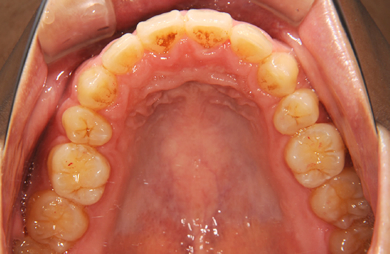

| 性別/年齢 | 男性 / 24歳 | ||||||||||||||||||||||||||||||||

| 主訴 | 乱ぐい歯を治したい。 | ||||||||||||||||||||||||||||||||

| 治療方針 | 歯のがたつきが大きいことより上下左右第一小臼歯を抜歯して、マルチブラケット装置にて治療。また、親不知がまっすぐ生えることができず横を向いている状態なので、まっすぐにする隙間があることから親不知も使用し、矯正を行う。 | ||||||||||||||||||||||||||||||||

| 治療内容 | 唇側矯正(ホワイト) | ||||||||||||||||||||||||||||||||

| 総治療費 | 663,810円 | ||||||||||||||||||||||||||||||||

| 治療期間 | 2ヶ月 |